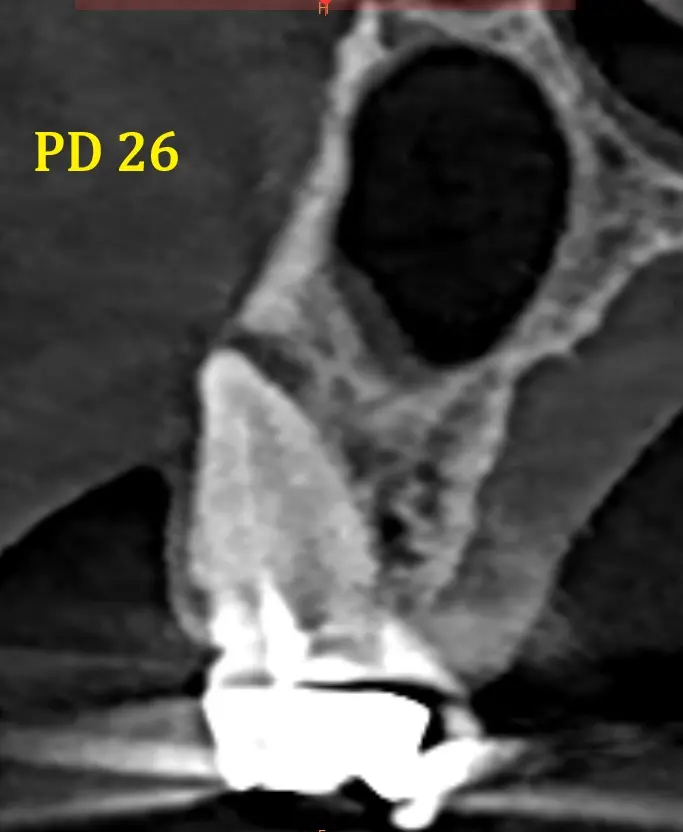

También en zona hemimaxilar izquierda se descubrió una lesión periapical en pieza dental 26, la raíz vestibulo mesial. que genera un leve engrosamiento de la membrana sinusal y fenestracion de tabla vesticular. (imagen 5)